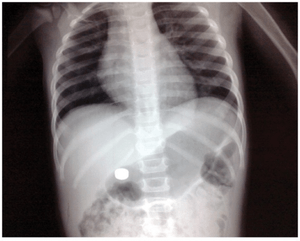

Gallstones (not sensitive)

Gallstones (not sensitive)